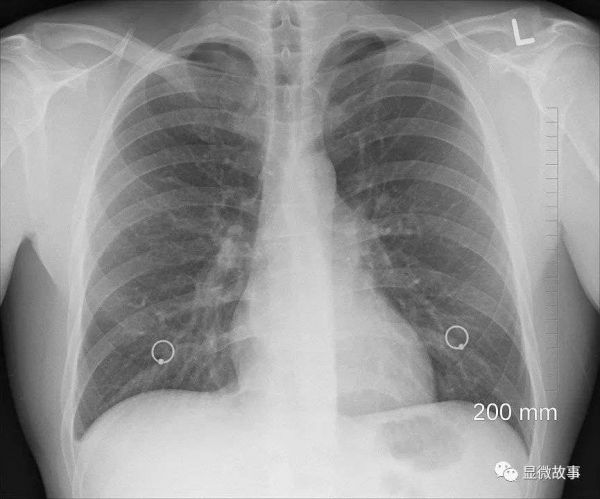

图 | 江华医生(右)和他的患者

孩子的小耳没有正常形态,只有个肉赘,且没有外耳道,我检查后发现他听力基本满足正常生活需求。

于是,我们给孩子制定了一个手术方案:第一期先埋一个扩张器,第二期再用软骨雕出支架来进行耳部再造,恢复孩子应有的耳朵形态。

图 | 江华医生(右二)和患者一家的合影